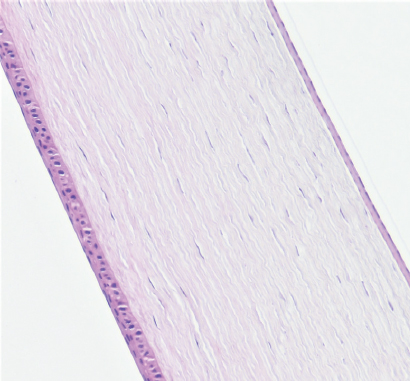

Режим 5. При данной мощности эпителий роговицы на всём протяжении имел обычное строение. Передние 10–15 % стромы в месте воздействия были незначительно разрыхлены. Десцеметова мембрана и энодотелий оставалась без изменений (рис. 3).

Рис. 3. Фрагмент роговицы после воздействия в подгруппе 1а. Фульгурация, режим 5. Окраска гематоксилином и эозином. Увеличение ×100

Fig. 3. Fragment of the cornea after exposure in subgroup 1a. Fulguration, mode 5. Stained with hematoxylin and eosin. Magnification ×100

На первом этапе эксперимента воздействие на роговицу в режиме 5 как клинически, так и гистологически выглядело недостаточным. Изменения охватывали лишь 10–15 % передней стромы. Учитывая, что в норме толщина роговицы кролика в центре составляет примерно 350 мкм, воздействию подвергались лишь около 50 мкм стромы. При воздействии в режиме 6 и 7 через 3 мес. изменения стромальной структуры распространялись примерно на 150 мкм. Воздействие в режиме 8, по нашему мнению, является избыточным. У кролика на этом режиме воздействия были самые грубые изменения в строме. Кроме того, в патологический процесс вовлекалась десцеметова мембрана.